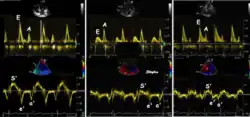

Like Doppler flow, tissue Doppler can be acquired both by spectral analysis (spectral density estimation) as pulsed Doppler[1] and by the autocorrelation technique as colour tissue Doppler[2] (duplex ultrasonography). While pulsed Doppler only acquires the velocity at one point at a time, colour Doppler can acquire simultaneous pixel velocity values across the whole imaging field. Pulsed Doppler on the other hand, is more robust against noise, as peak values are measured on top of the spectrum, and are unaffected of the presence of clutter (stationary reverberation noise).

As the ventricle relaxes, the annulus moves towards the base of the heart, signifying the volume expansion of the ventricle. The peak mitral annular velocity during early filling, e' is a measure of left ventricular diastolic function, and has been shown to be relatively independent of left ventricular filling pressure.[12][13][14] If there is impaired relaxation (Diastolic dysfunction), the e' velocity decreases. After the early relaxation, the ventricular myocardium is passive, the late velocity peak a' is a function of atrial contraction. The ratio between e' and a' is also a measure of diastolic function, in addition to the absolute values.

During the two filling phases, there is early (E) and late (A) blood flow from the atrium to the ventricle, corresponding to the annular velocity phases. The flow, is driven by the pressure difference between atrium and ventricle, this pressure difference is both a function of the pressure drop during early relaxation and the initial atrial pressure. In light diastolic dysfunction, the peak early mitral flow velocity E is reduced in proportion to the e', but if relaxation is so reduced that it causes increase in atrial pressure, E will increase again, while e', being less load dependent, remains low. Thus, the ratio E/e' is related to the atrial pressure, and can show increased filling pressure[15][16] although with several reservations.[17][18] In the right ventricle this is not an important principle, as the right atrial pressure is the same as central venous pressure which can easily be assessed from venous congestion.[19][20]